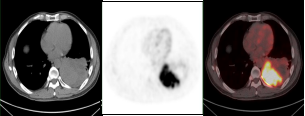

1.2放疗前确定肿瘤病灶生物靶区,提高放疗疗效

肺癌放疗前确定生物靶区:左肺下叶鳞癌患者(右图所示),左下肺癌病灶并远端阻塞性肺不张,PET/CT可以准确区分肿瘤组织与非肿瘤组织,确定肿瘤病灶生物靶区。